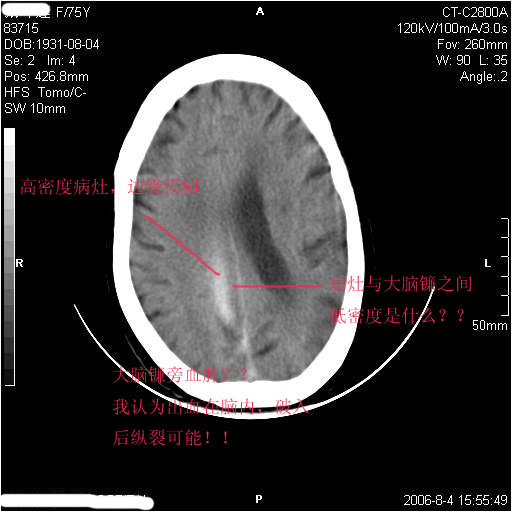

左侧偏瘫3天.

1纵裂硬膜下血肿,2双基底节脑软化灶.

1、纵裂硬膜下血肿,2、右侧室前角旁梗塞;3、双基底节脑软化灶.

镰旁慢性硬膜下出血?双侧多发腔梗。

有摔倒外伤史,另看右侧灰白质界限.

双侧基底节区多发性腔梗.引起临床症状的主要原因是右侧侧脑室旁的梗塞病灶.

应该是右侧大脑镰旁的血肿,右侧基底节区脑梗塞。

1、该患者从脑实质表现情况看应该年龄较大了,双侧基底节区多发斑片状低密度灶,侧脑室旁白质密度减低,各脑室腔扩大,脑沟裂增宽加深,以上改变符合:皮层下动脉硬化性脑病。

2、上纵裂右侧梭形条状高密度影阴,边缘模糊,周围水肿带环绕,右侧脑室受压变形,有摔倒外伤史,多考虑:纵裂硬膜下血肿。

支持纵裂硬膜下血肿,应该是慢性,或是再出血.

该是右侧大脑镰旁的血肿,双侧基底节区脑梗塞

右侧大脑镰旁的血肿,右侧基底节区脑梗塞。